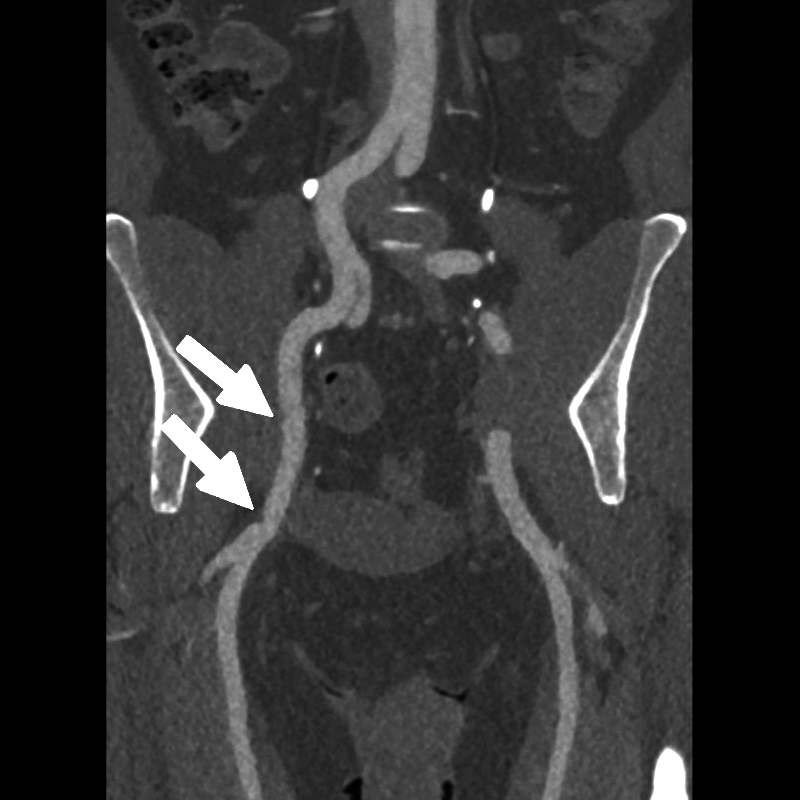

When the patient moved into the stressed position, the right external iliac artery showed two areas of luminal narrowing (a temporary decrease in the size of the vessel’s opening). One narrowing was more proximal (closer to the vessel’s origin near the pelvis) at about ten to twenty percent, and the second was more distal (farther along the vessel toward the leg) at about thirty to forty percent. Both returned to a widely patent appearance (fully open) when the leg moved back to a relaxed position.

The left external iliac artery remained patent across positions, and the common iliac arteries were tortuous (naturally curving) without any fixed stenosis. This pattern aligns with external iliac endofibrosis, where motion causes the artery to change shape rather than a fixed obstruction, highlighting why positional imaging can reveal abnormalities that may not appear on routine resting studies.

Figure J (Right): Two areas of narrowing were identified in the right external iliac.